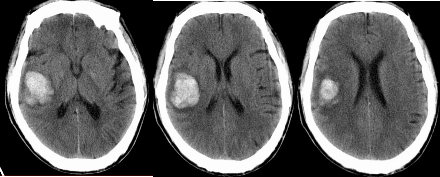

丘脑出血

责任血管:大脑后动脉垂直分出的管壁薄弱的终末支丘脑膝状体动脉和丘脑穿通动脉,为脑出血的好发部位,仅次于壳核

病因:高血压动脉硬化,微小动脉瘤或血管畸形,血液病

症状体征: